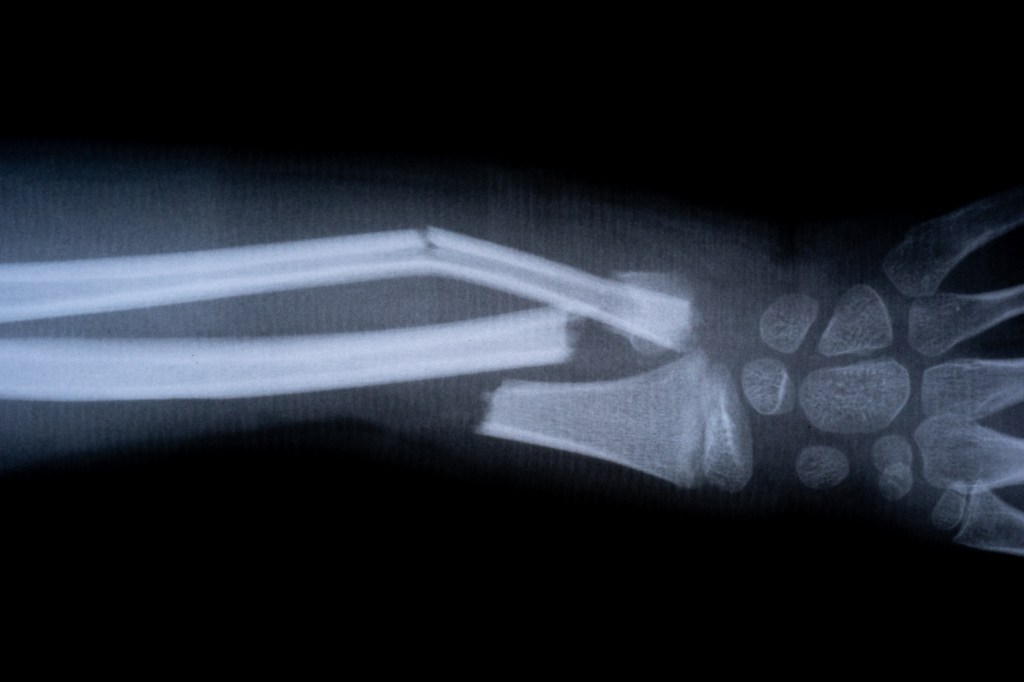

In one trial, a patient with a wrist fracture was treated through a small incision and healed in minutes — avoiding the need for plates, screws, and follow-up surgeries. Three months later, doctors confirmed the bone had healed fully without complications.